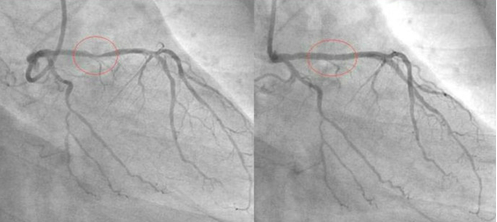

冠状动脉造影是诊断冠状动脉粥样硬化性心脏病(冠心病)的一种常用而且有效的方法,被称为诊断冠心病的“金标准”。心电图显示缺血,有心闷、气短、胸痛等心肌梗死先兆时,要做个冠状动脉造影检查,以便及时发现及时治疗,避免心肌梗死发生。

他是一位虔诚的回教徒,为了让更多的人受益,他把自己的经验放在网上分享,他的前后两张血管照片也放了在网上,在他的冠状动脉造影照片中,服用食疗之前与之后的分别连普通人也看得出来。